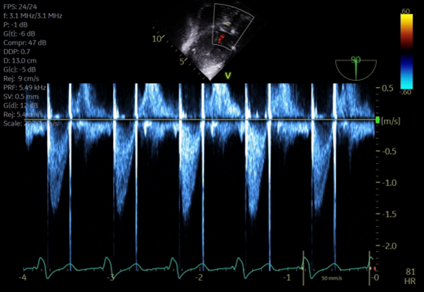

Scenario: 17yo m w/ pmh bicuspid aortic valve with mixed stenosis and regurgitation and dilated aortic root presents for Ross procedure. His pre-operative TEE exam revealed the following

Image 1

1.  What midesophageal TEE views are shown in images 1 and 2?

Image 1 is a mid-esophageal long axis view, typically found at an omniplane angle around 120 degrees. Image 2 is a mid-esophageal aortic valve short axis view, typically found at an omniplane angle between 30 and 60 degrees.